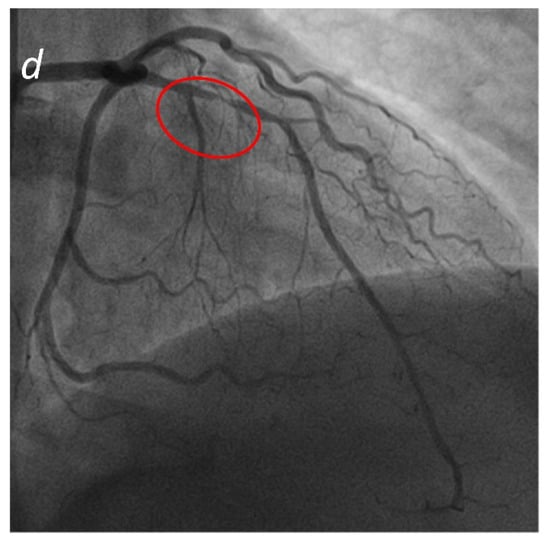

Figure 3.

MINOCA-Miocardial Infarct non obstructive coronaries. The patient presented to the emergency department with acute chest pain, ECG and cardiac enzymes suggestive of STEMI in the lateral wall of the left ventricle. The patient was readily referred to coronary angiography and cardiac catheterization showed absence of obstructive stenoses in the coronary tree (a). One day later a cardiac MRI was performed demonstrating a subacute ischemic scar in the lateral wall of the medium-apical left ventricle ((b)-LGE short axis view, (c)-LGE four chambers view). In the context of transmural late gadolinium enhancement, a constantly hypointense central area is present, representing a microvascular obstruction zone (red arrow). A cardiac CT was subsequently performed in order to assess coronary wall features and the presence of atherosclerosis. CT images in volume rendering (d) and multiplanar oblique reconstruction (e) demonstrated a non-calcified atherosclerotic alteration in an obtuse marginal vessel, serving the infarcted zone. A partly calcified atherosclerotic pathology was present in the anterior descending artery.